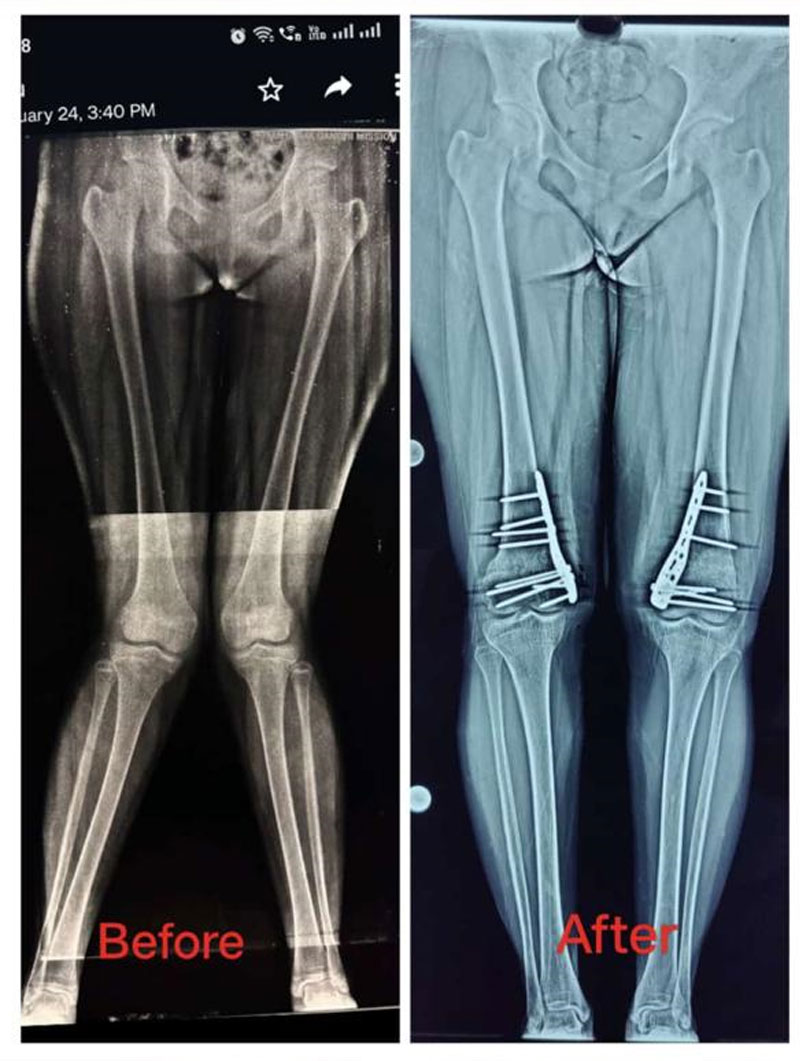

Deformity Correction